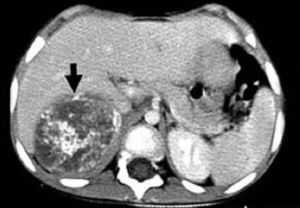

Компьютерная томография более детально дает информацию об анатомическом отношении опухоли к окружающим тканям и органам, позволяет оценить структуру опухоли (рис. 5).

Рис. 5. КТ нейрогенного образования забрюшинного пространства справа